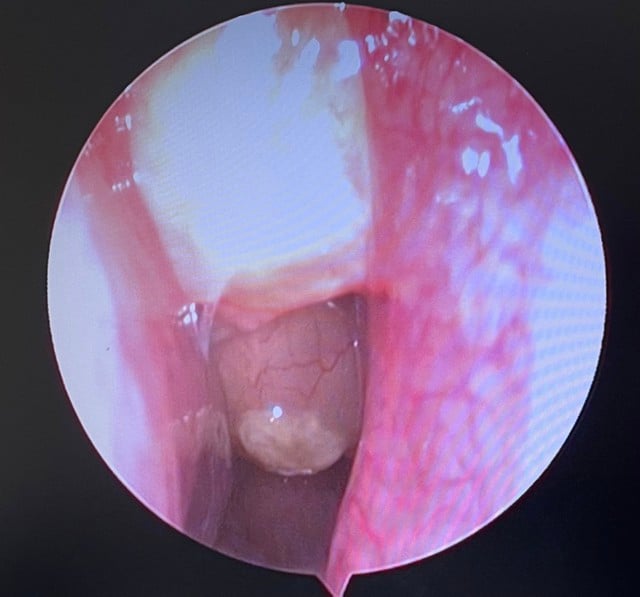

យោងតាមវេជ្ជបណ្ឌិត ការវះកាត់នេះបានបង្ហាញពីបញ្ហាប្រឈមជាច្រើន ដូចជាប្រហោងឆ្អឹងអេតម៉យរបស់អ្នកជំងឺមានជញ្ជាំងឆ្អឹងរលាកក្រាស់ខុសប្រក្រតីនៅកន្លែងខ្លះរហូតដល់ប្រហែល 1 មីលីម៉ែត្រ ដែលធ្វើឱ្យការបើកប្រហោងឆ្អឹងពិបាក និងត្រូវការភាពជាក់លាក់ដាច់ខាតនៅគ្រប់ជំហាន។ លើសពីនេះ មានហានិភ័យខ្ពស់នៃការហូរឈាមអំឡុងពេលវះកាត់ ពីព្រោះអ្នកជំងឺត្រូវឈប់ប្រើថ្នាំប្រឆាំងការកកឈាមមុនពេលវះកាត់។

យោងតាមលោកវេជ្ជបណ្ឌិត Nguyen Hy Quang អ្នកឯកទេសផ្នែកត្រចៀកច្រមុះបំពង់ក នៅមន្ទីរពេទ្យ E ក្នុងអំឡុងពេលនៃការវះកាត់ ក្រុមត្រូវកែសម្រួលយុទ្ធសាស្ត្រជានិច្ច និងប្តូរផ្នែកវះកាត់ដោយបត់បែន ដើម្បីបង្កើនប្រសិទ្ធភាពពេលវេលា និងកាត់បន្ថយហានិភ័យ ដោយសារស្ថានភាពសរសៃឈាមបេះដូងស្មុគស្មាញរបស់អ្នកជំងឺ។ ជាពិសេស នៅផ្នែកខាងស្តាំ ម៉ាសឆ្អឹងក្រាស់អាចត្រូវបានយកចេញបន្តិចម្តងៗ ដោយប្រើដង្កៀប Kerrison ដែលទាមទារការអត់ធ្មត់ និងបទពិសោធន៍ពីគ្រូពេទ្យវះកាត់។

បន្ទាប់ពីការវះកាត់ ដុំសាច់ប៉ូលីប និងភ្នាសរំអិលដែលខូចទ្រង់ទ្រាយទាំងអស់នៅក្នុងប្រហោងច្រមុះខាងលើ ប្រហោងច្រមុះអេតម៉យទ្វេភាគី និងប្រហោងច្រមុះខាងស្តាំត្រូវបានយកចេញ។ ប្រហោងច្រមុះដែលរលាកត្រូវបានសម្អាត ដើម្បីធានាបាននូវការបង្ហូរទឹក និងខ្យល់ចេញចូល។ ការវះកាត់មានសុវត្ថិភាព ដោយគ្មានផលវិបាកណាមួយត្រូវបានកត់ត្រាទុកឡើយ។ 2.5 ថ្ងៃបន្ទាប់ពីការវះកាត់ ស្រទាប់ Merocel និងស្រទាប់ច្រមុះទាំងអស់ត្រូវបានយកចេញ អ្នកជំងឺមិនមានការហូរឈាមឡើងវិញទេ ផ្លូវដង្ហើមស្អាត ហើយការដកដង្ហើមមានស្ថេរភាព។